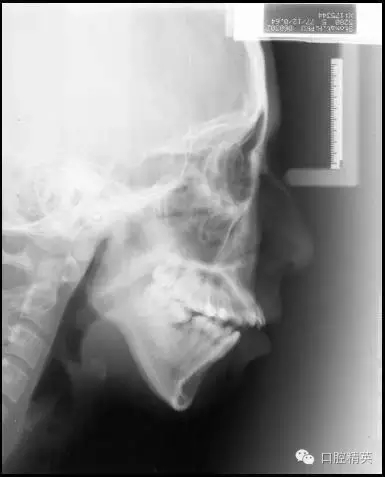

既然我們很難改變患者髁突生長不足的問題,就只好從控制其上頜骨及磨牙區(qū)的垂直生長著手了,由于抑制生長本非易事,控制患者的磨牙高度就成了控制其下頜平面最切實可行的手段。而通過壓低磨牙來控制高角患者的下頜平面,乃至實現(xiàn)其下頜平面的前上旋轉(zhuǎn)正是后部垂直向控制的概念及意義所在(圖1)。

圖1 通過壓低磨牙進行后部垂直向控制

前部垂直向控制則是指控制上前牙向上向后移動。 這一概念源于Tweed-Merrifield技術(shù)的方向性力系統(tǒng)。這一技術(shù)一直被認為能夠為Ⅱ類高角患者帶來最佳的矯治效果,技術(shù)標志之一就是著名的方向性力系統(tǒng),即通過控制患者的下后牙和上前牙來控制其下頜平面和合平面,實現(xiàn)這一控制的所有力的合力矢量均需向上向前,所需方向性力由牽引皮圈和可調(diào)整方向的J鉤頭帽提供。最終實現(xiàn)下切牙直立于基骨之上,上前牙向上向后移動,為下頜骨的前上旋轉(zhuǎn)創(chuàng)造條件,而這也正是前部垂直向控制的概念及意義所在(圖2)。

Ⅰ類或Ⅱ類高角,前牙開合,但前牙垂直向唇齒關(guān)系正常,即沒有露齦微笑。這類高角病例將最直接而有效地發(fā)揮微螺釘種植體支抗在垂直向上的優(yōu)勢。在后部,應(yīng)用微螺釘進行后部垂直向控制,壓低后牙,解除支點,下頜平面前上旋轉(zhuǎn),前牙開合關(guān)閉。在前部,因為沒有露齦微笑的問題,上前牙并不需要實現(xiàn)絕對壓低,僅需保持住其垂直向位置,阻止因上前牙的伸長而導(dǎo)致下頜平面前上旋轉(zhuǎn)的空間減小。

因此,即使對于拔牙病例因鐘擺效應(yīng)上前牙有伸長趨勢,通過直絲弓矯治技術(shù)中的搖椅弓也能夠很好地實現(xiàn)前部的垂直向控制。這類高角患者的全方位垂直向控制充分說明,后部垂直向控制,即磨牙的絕對壓低或相對壓低(向遠中直立或阻止其伸長)是實現(xiàn)下頜平面前上旋轉(zhuǎn)的必要條件,而后上移動上前牙的前部垂直向控制并不是必需的,僅需控制即可,甚至上前牙稍有伸長,因為沒有露齦微笑,只要下頜平面可以前上旋轉(zhuǎn)到一個理想的位置,頦部位置和形態(tài)得到顯著的改善,也是完全可以接受的。